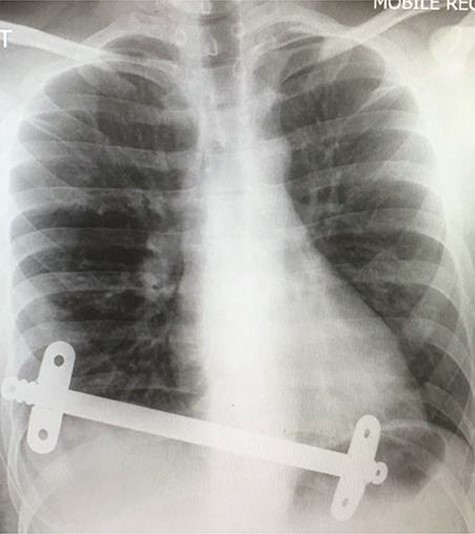

Superior intraoperative view of the laparotomy used to access and remove the second migrated bar.

Our patient was followed up annually. After two and half years, he developed a right-sided wound infection, initially treated with antibiotics. It was decided to remove the bar for prevention of recurrent infection. The chest X-ray showed migration of the lower-placed bar (Fig. 2). The upper bar and associated stabilizers were removed through the bilateral small incisions without any complication; however, the lower bar was not palpable. Therefore, a left-side thoracotomy was performed; however, the bar was not found in the chest. The incision was extended to a midline laparotomy (Fig. 3). This revealed an erosion of the bar in to the stomach after passing over the left lobe of the liver (Fig. 4). The bar and stabilizers were completely removed, and the hole in the stomach was closed directly with sutures. The patient was discharged home without any further complication after successful recovery.